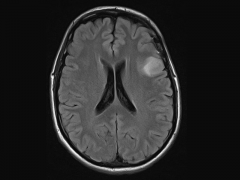

弥漫性浸润性低级别胶质瘤管理

根据国际卫生组织(WHO)2016年对中枢神经系统肿瘤分类的更新,成...